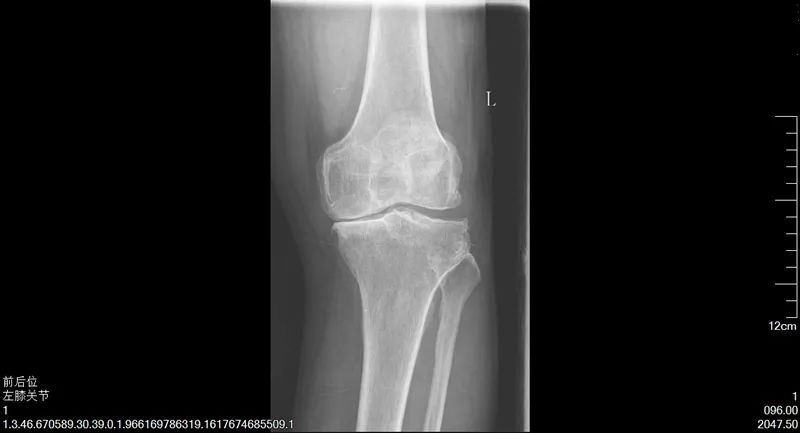

陳阿姨的故事,說來還要將時間追溯至十年前,陳阿姨常年操持家中的生意,雙膝落下了問題,時常疼痛難忍,后來甚至發(fā)展至不能正常行走。這時,鄰居常大哥告訴她,可以試試到市第一人民醫(yī)院看看。隨即,陳阿姨來到了我院骨科二病區(qū)找到了楊勇主任,做了雙側(cè)人工全膝關(guān)節(jié)置換術(shù),術(shù)后恢復(fù)得非常好,雙腿和正常人無異,既不疼了,也能站直了。時至今日,陳阿姨說她的腿依然健康如初,每天可以去跳廣場舞,生活質(zhì)量得到了顯著提高。

手術(shù)前

同時聽陳阿姨介紹,鄰居常大哥也是因患有類風(fēng)濕性關(guān)節(jié)炎,雙膝關(guān)節(jié)屈曲,不能伸直,疼痛不能行走,病情比陳阿姨更為嚴(yán)重,經(jīng)楊主任手術(shù)后,雙腿恢復(fù)正常,生活質(zhì)量大大提高。